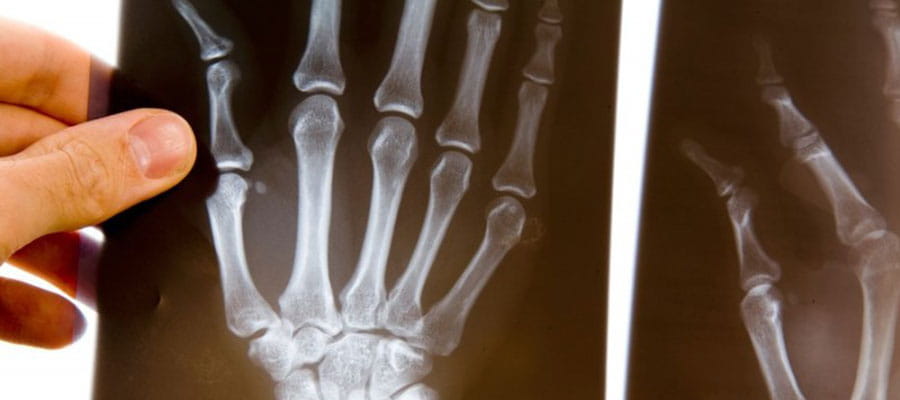

- рентген стоп и кистей, КТ, МРТ, а также УЗИ других органов;

Что касается костей и суставов, то человек может наблюдать скованность движений, невозможность быстро согнуть и разогнуть конечность, а также отечность. Доходит до того, что в некоторых областях кости небольшого размера могут даже рассасываться, вызывая искривления и другие неприятные последствия. Из-за нарушений суставной подвижности некоторые мышцы могут атрофироваться или значительно ослабевать.